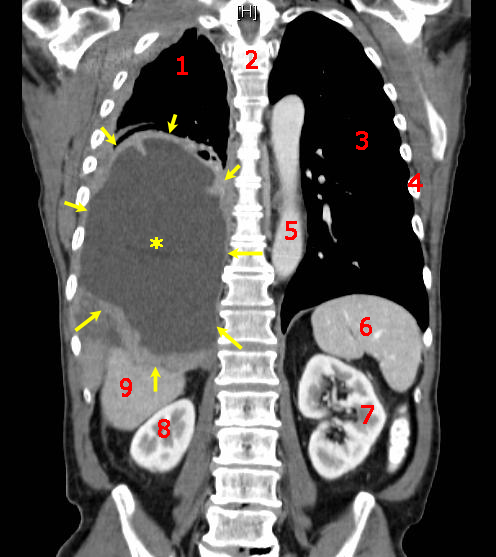

悪性腫瘍(あくせいしゅよう、Malignant Tumor, Cancer)は、生体の自律制御を外れて自己増殖する細胞集団である。周囲の組織に浸潤して転移する腫瘍を指す。がん(ガンまたは癌)や「悪性新生物」とも称し、死亡につながることも多い。国立がん研究センターによると、2007年以降に登録された院内がんデータでは、2018年の時点で10年生存率は59.4%であり、部位や病期(「ステージ」)により差が大きい。 なお漢字の「癌」と平仮名の「がん」は医学的には使い分けられている場合がある。その場合、「癌」は皮膚癌、肝臓癌、膵臓癌、子宮癌などのように上皮細胞から発生する悪性腫瘍に限って使い、からだの外とつながっていない骨や筋肉などがガン化したものは肉腫と呼ぶなどし区別するが、これらを含め「がん」はすべての悪性腫瘍を指す。